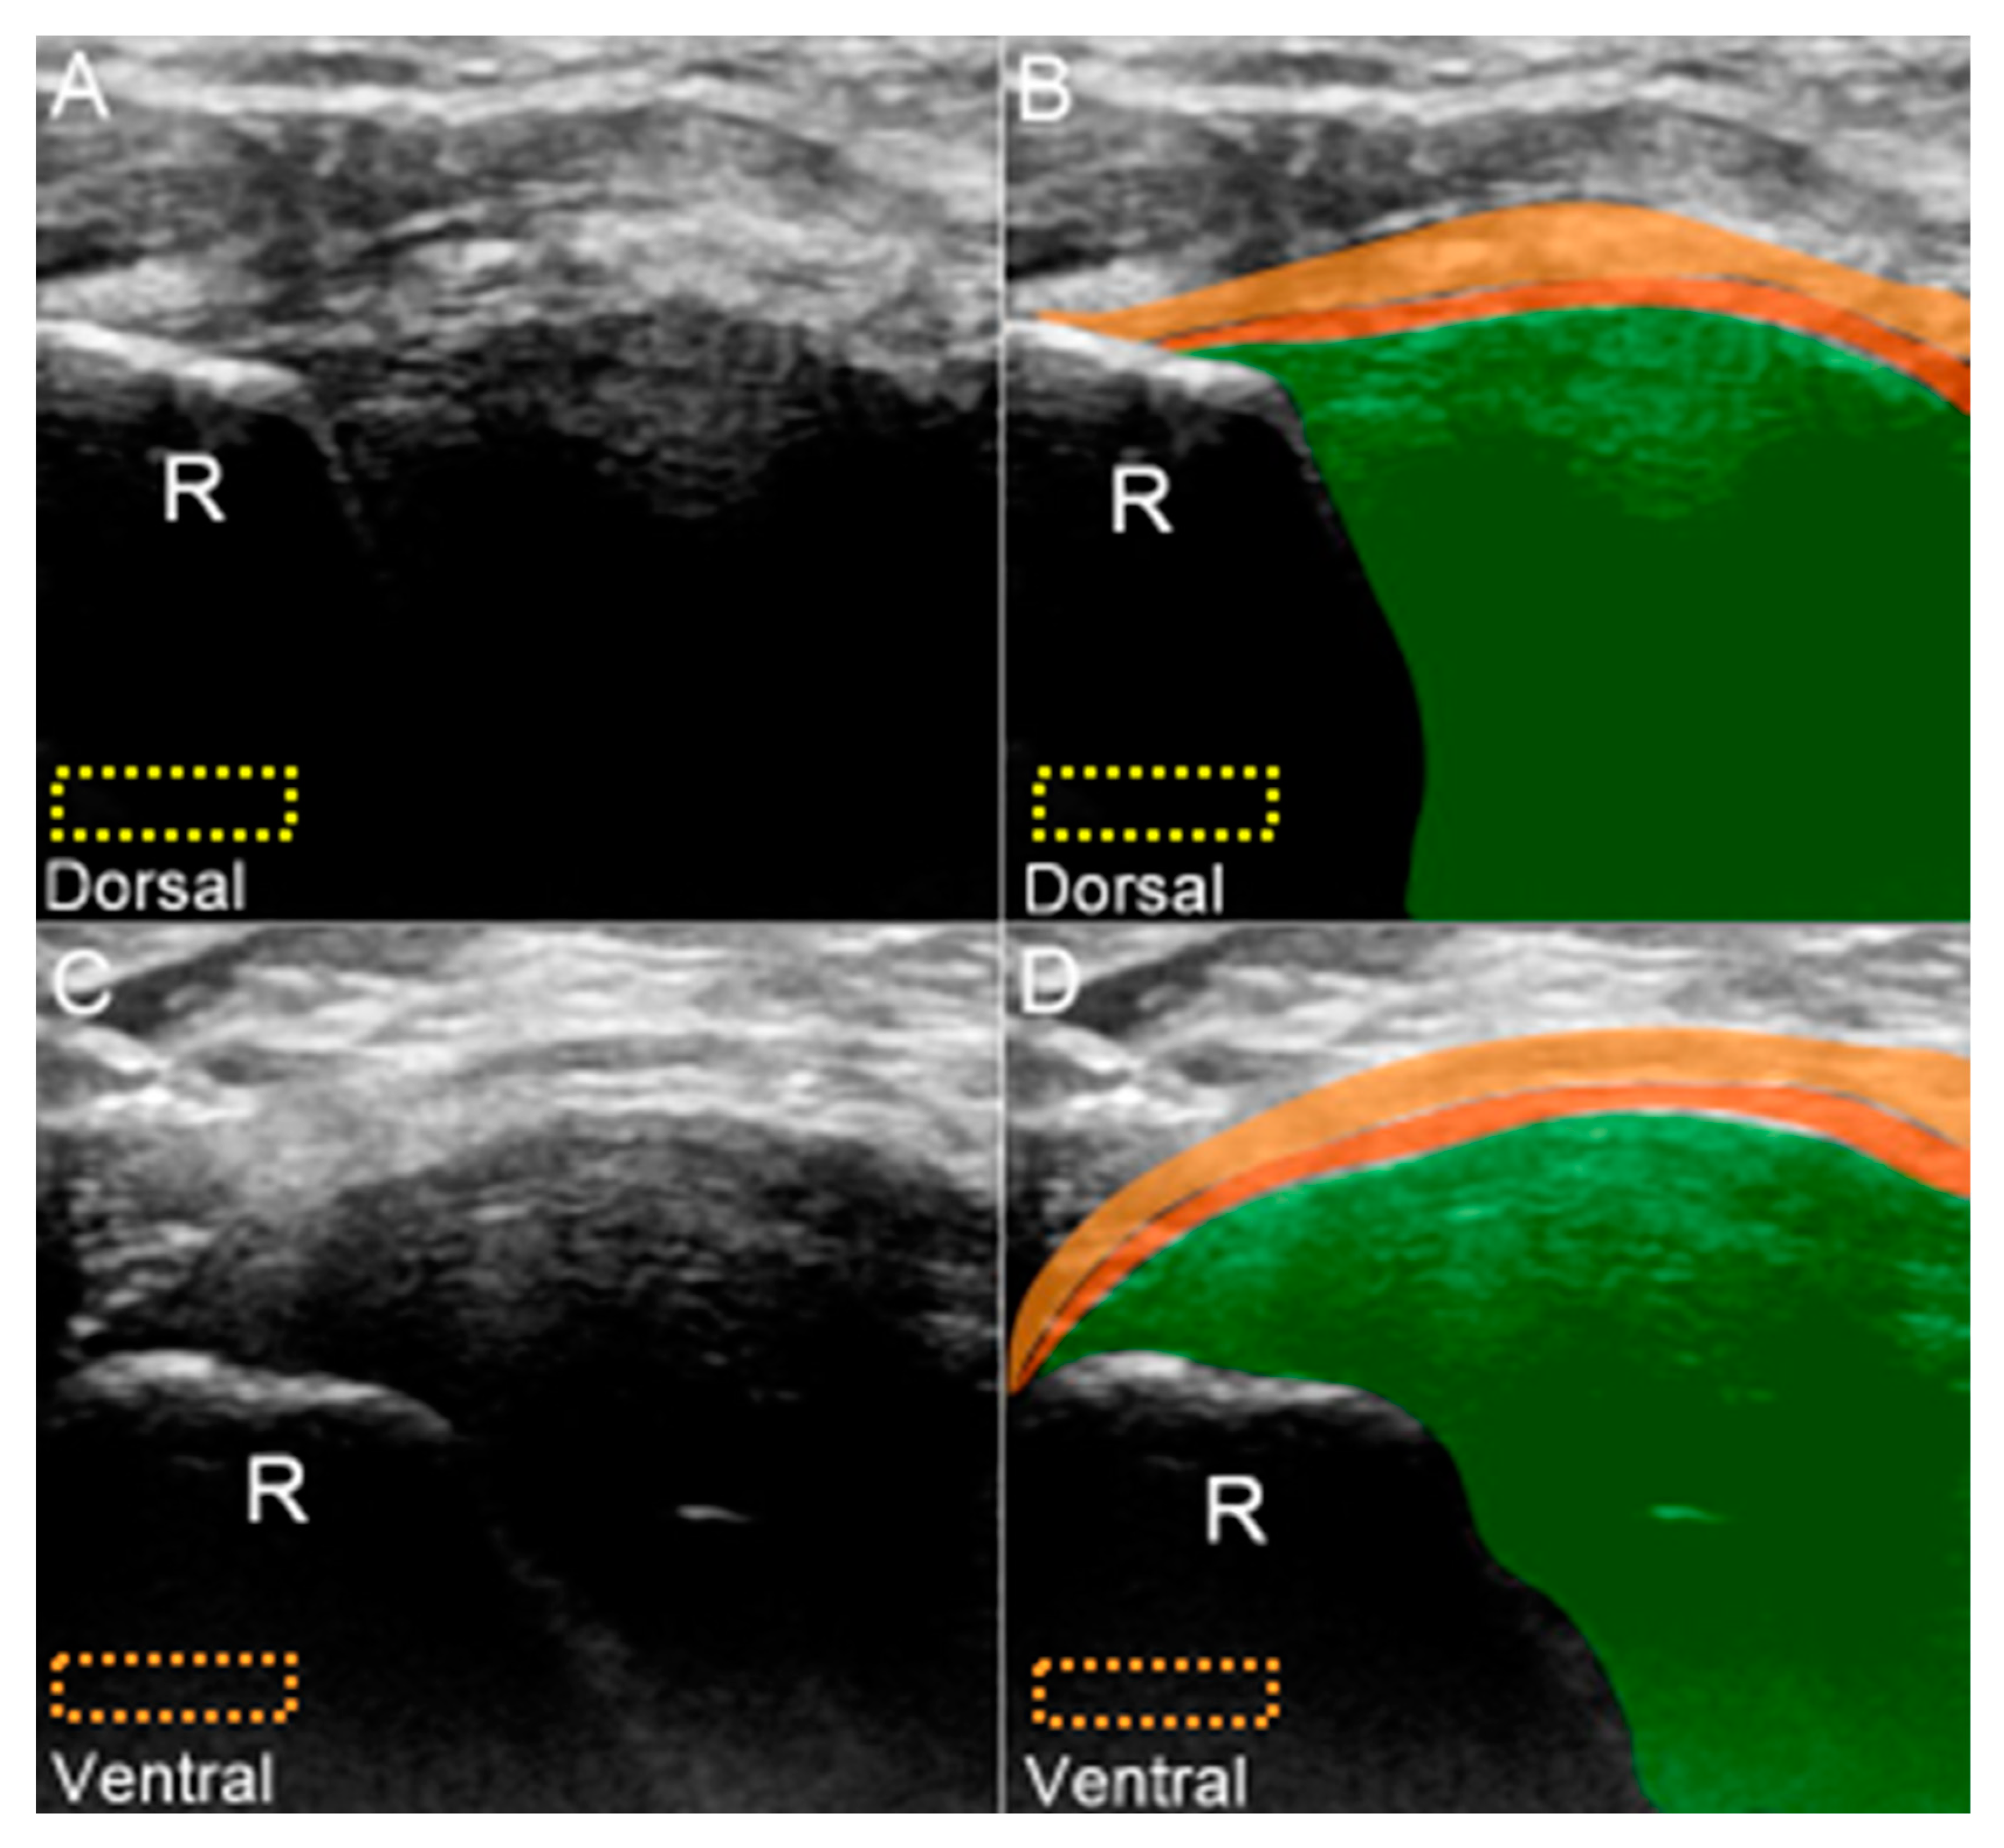

6. US Imaging

6.1. Scanning Protocol

6.1.1. Long-Axis View